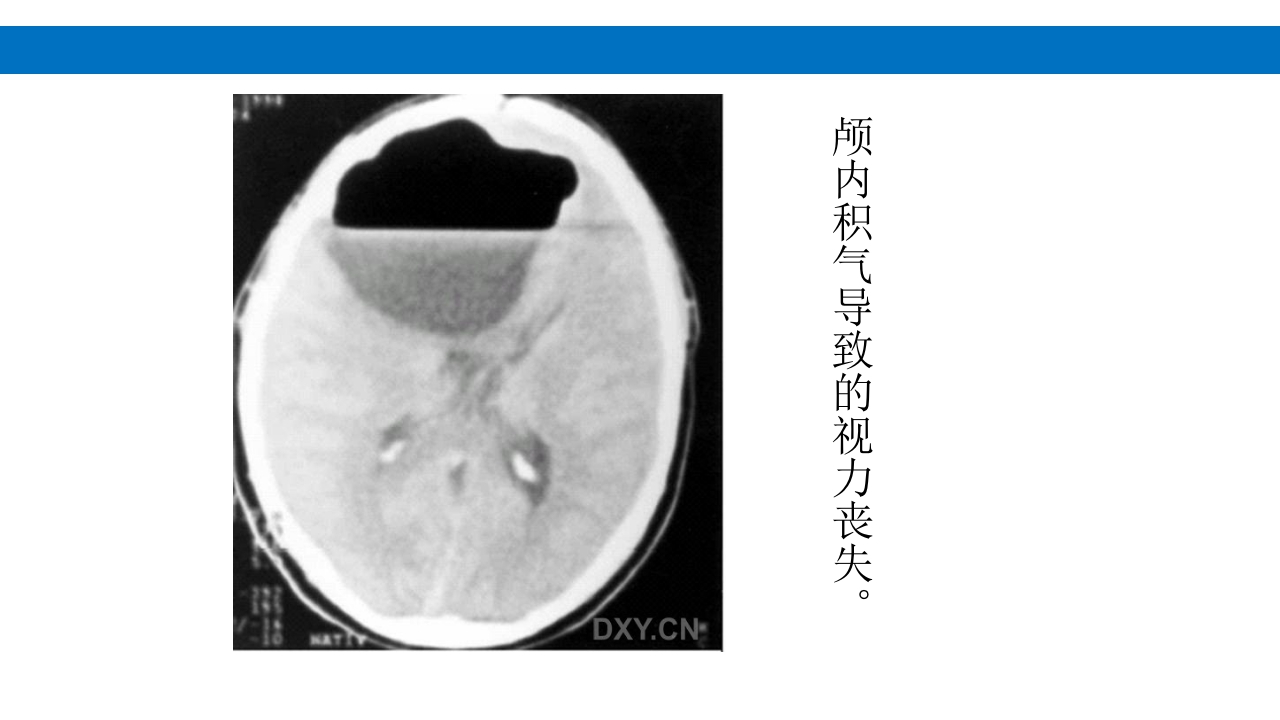

颅脑损伤的并发症及后遗症 讲解人:xxx 20XX年x月x日 1.颅骨骨髓炎 病因:为头皮软组织、中耳、乳突和副鼻窦等处炎性感染而经导 血管侵入颅骨内或颅脑开放伤感染所引起,亦可由菌血症后发生 的细菌栓子由血运转移至颅骨内。 影像学表现: 头部CT: 1.表现为不规则的蜂窝状骨质破坏区,主要位于板障,亦可累 及内外板。 2.破坏区内可见高密度的米粒状细小的高密度死骨。 3.周边可见骨质硬化增生,颅板外无骨膜反应。 4.局部的头皮可见软组织肿胀。 头部MRI: 由于受累部位细胞成分和水量增多,T1WI为低信号, T2WI为高信号,急性期边界不清,慢性期病灶局限, 边界清晰。MRI显示骨质破坏没有CT效果好。 治疗: 除应用抗菌药物控制感染外,当感染局限或已有死骨形成后, 应行手术切除感染...